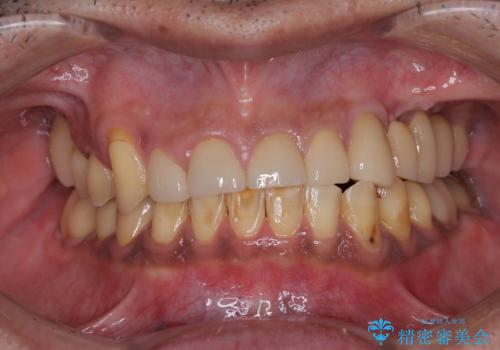

仮歯のまま放置した前歯 オールセラミッククラウンで自然な前歯に

- 仮歯装着後に放置してしまい、恥ずかしいとのことで来院された患者様です。

仮歯が不適合で歯肉が腫脹していたため、しっかりと調整した新しい仮歯にして腫れを改善した上で、オールセラミッククラウンにて補綴することとしました。

日頃の歯磨きをしっかりと行ってくださるので、新しい仮歯に変えてから速やかに歯肉の状態が改善されました。

歯肉からの出血がほとんどないため精度の良い型取りができ、非常に適合の良い補綴治療を行うことができました。